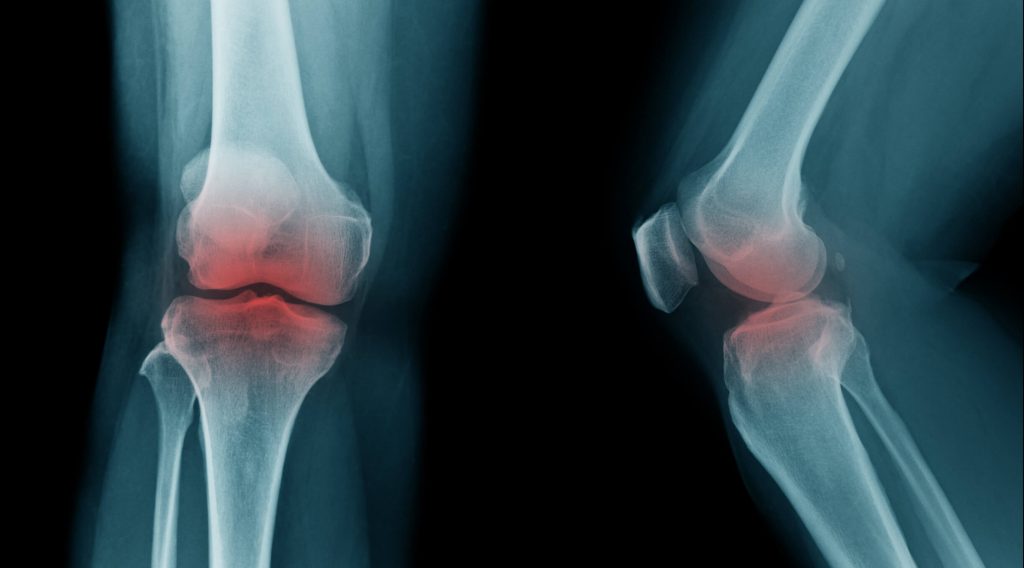

استفاده از متفورمین با کاهش خطر استئوآرتریت ارتباط دارد

محققان دریافتند که در مقایسه با شرکت کنندگانی که یک سولفانیل اوره مصرف کردند، کسانی که متفورمین مصرف کردند ۲۴ % احتمال کمتری برای ابتلا به استئوآرتریت داشتند. همچنین احتمال اینکه آنها تحت تعویض مفصل قرار گیرند نیز ۲۰ % کمتر بود، اما این تفاوت دوم از نظر آماری معنیدار نبود، به این معنی که این امر میتواند ناشی از شانس به تنهایی باشد. برای تایید یافتههای خود، محققان آنچه را که به عنوان تحلیل حساسیت در این مورد شناخته میشود، انجام دادند، آنها نتایج را تنها با نگاهی به شرکت کنندگانی که تنها متفورمین یا سولفونیل اوره را به عنوان داروی دیابت مصرف کرده بودند، محاسبه کردند. نتایج تجزیه و تحلیل حساسیت نشان داد که مصرف متفورمین با ۲۳ %ذخطر کم تر ابتلا به استئوآرتریت همراه با ۴ % شانس بیشتر برای جایگزینی مفصل مرتبط است.